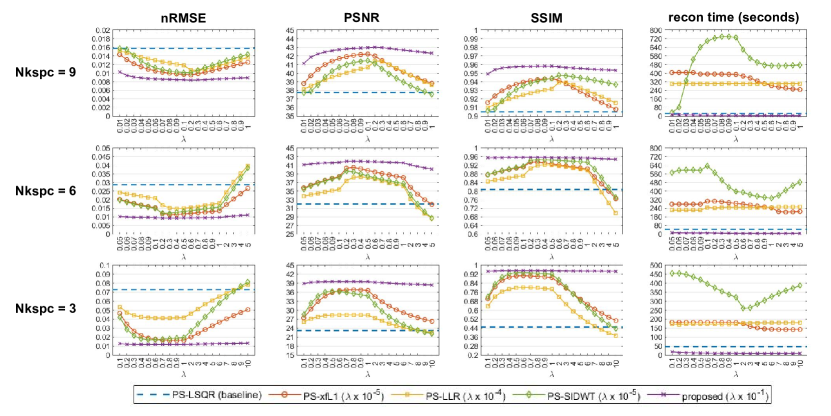

4.3.2 Comparative Study on

A brute-force search for the best was performed for each PS model algorithm. The search range of regularization coefficient was fixed as for Nkspc=9, for Nkspc=6, and for Nkspc=3. For PS-xfL1, the search range was multiplied by . For PS-LLR, the search range was multiplied by . For PS-SIDWT, the search range was multiplied by . For the proposed model, the search range was multiplied by . Scaling of the search range guarantees that is suitable for each algorithm. Image reconstruction was performed for each combination of and Nkspc values. Image quality metrics of nRMSE, PSNR, SSIM and the reconstruction time were recorded.

5.2.2 Comparative Study on

The results about the search for the best is shown in Figure 6. The best has already been discovered for each model. The proposed method has the lowest mean nRMSE, the highest mean PSNR, the highest mean SSIM, and the lowest mean reconstruction time at each given . This indicates that the proposed method outperforms other models in a systematic level. Besides, when Nkspc is reduced, the gap between the curve peak of proposed method and other models increases, which means the proposed method displays stronger superiority when the acquisition time is shortened. Finally, the curve of proposed method is relatively flat compared with other methods, which implies the proposed method has stronger robustness against the hyper-parameter .

Comprehensively considering the quantitative metrics, the best is chosen for each model. (For Nkspc=9, for PS-xfL1, for PS-LLR, for PS-SIDWT, and for the proposed method. For Nkspc=6, for PS-xfL1, for PS-LLR, for PS-SIDWT, and for the proposed method. For Nkspc=3, for PS-xfL1, for PS-LLR, for PS-SIDWT, and for the proposed method). Detailed quantitative metrics at the the best value are listed in Table 1.